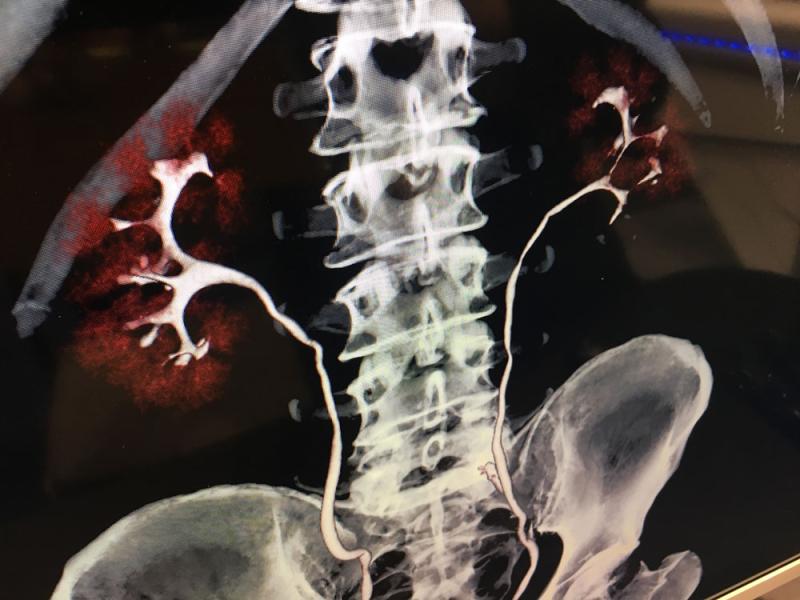

Below are photos from the American Society for Radiation Oncology (ASTRO) 2019 meeting September 2019 in Chicago. The annual conference has about 12,000 attendees. It is a showcase of the latest advances in radiation oncology technologies. Below are images of some of these radiation therapy technologies from the ASTRO expo floor with captions explaining them.